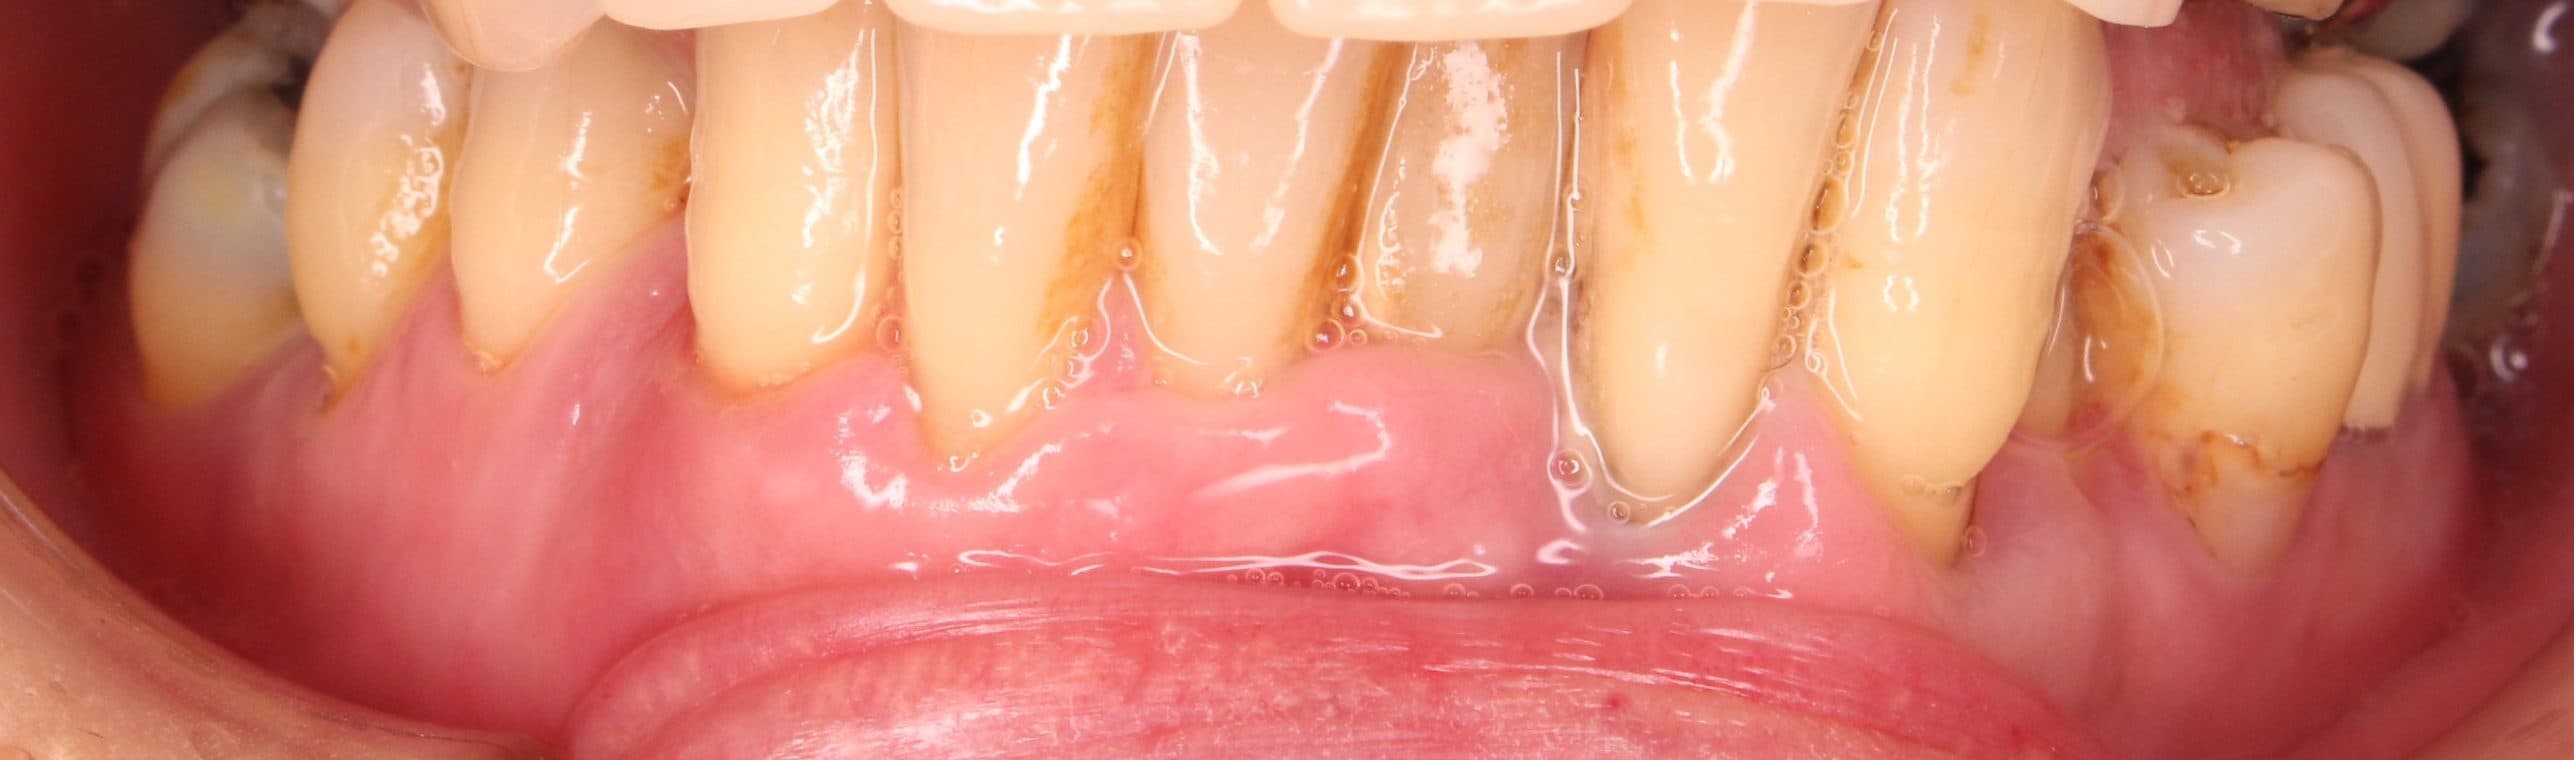

術後

術前

歯肉にのっているだけの歯の動きを完全に止める事は出来ませんが、治療後は日常の不便も無く、生活を送れるとのことでした。

可能な限り、現状維持が長く続くよう1か月に1度のメインテナンス管理を行っていきましょう!